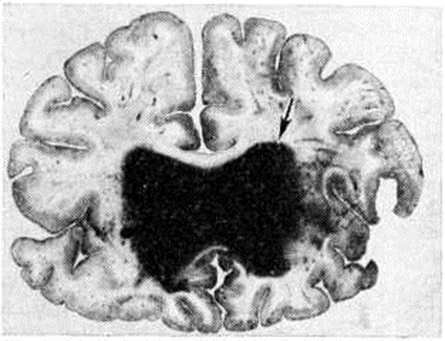

Рис. 4.

Фронтальный срез головного мозга на уровне зрительных бугров с «латеральным» кровоизлиянием (стрелкой указана гематома) в левом полушарии мозга.